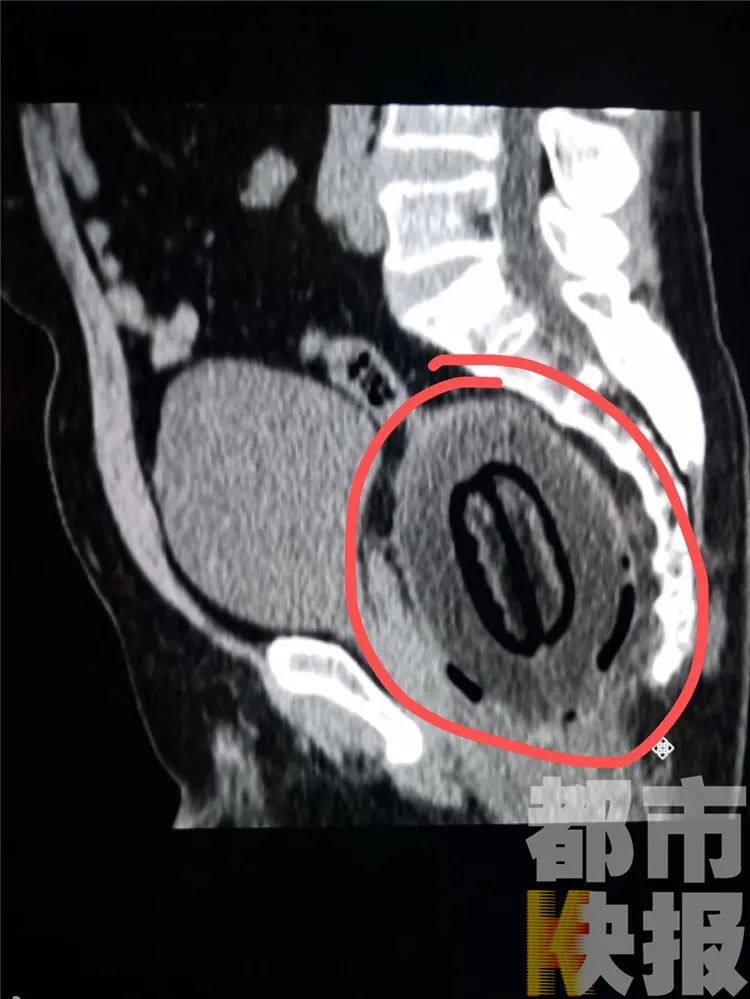

醫(yī)生注意到,男子說(shuō)話吞吞吐吐,連凳子都坐不下去,腹部摸著沒(méi)啥異樣,不過(guò)拍了片子后就發(fā)現(xiàn)問(wèn)題了。

西安國(guó)際醫(yī)學(xué)高新醫(yī)院普外科主任周亮:“患者的直腸內(nèi)有個(gè)特別巨大的異物,當(dāng)時(shí)看到這個(gè)異物,我們都特別特別驚訝!

巨大的異物就在直腸末端

西安國(guó)際醫(yī)學(xué)高新醫(yī)院普外科主任周亮:“手術(shù)持續(xù)六七個(gè)小時(shí),我們?cè)緡L試從肛門(mén)取出,但無(wú)法進(jìn)行,只能開(kāi)腹手術(shù),把異物取出。異物長(zhǎng)20多厘米,直徑十厘米左右,表面光滑,質(zhì)地非常硬!